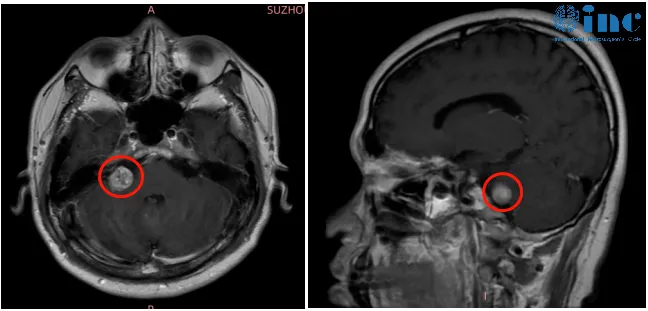

听神经瘤作为桥小脑角区最为常见的肿瘤,临床表现多样,比如听力下降、耳鸣、头痛、平衡失调,面部疼痛和麻木,这类肿瘤多见于30岁至60岁人群,很少见于年轻患者。 本期要分享的病例是...